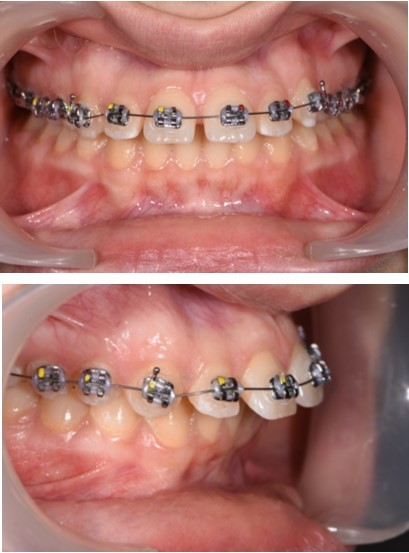

The working stage of the treatment was done with the use of a rectangular stainless steel archwire 0.019”x0.025” (Figure 5, Figure 6). Bodily movement was obtained and a minor intrusion. The incisal edges were displaced backward in order to provide a better incisal display at rest and during the smile. Unlike palatal arches, where the retraction is done by tipping the incisors, the mini implants in our case were able to provide a bodily retraction of the upper anterior teeth. Therefore, retraction was obtained with no anchorage loss. The improvement in the overjet and overbite was good.

Figure 5.Retraction of the upper incisors with elastics chains placed from crimpable hooks to orthodontic implants.

Figure 6.Significant overjet and overbite improvement after implant based orthodontic retraction.

The labial inclination of the incisors was corrected and better torque values were obtained. With the use of the temporary anchorage devices, a total of 7 mm of retraction was done in this case.